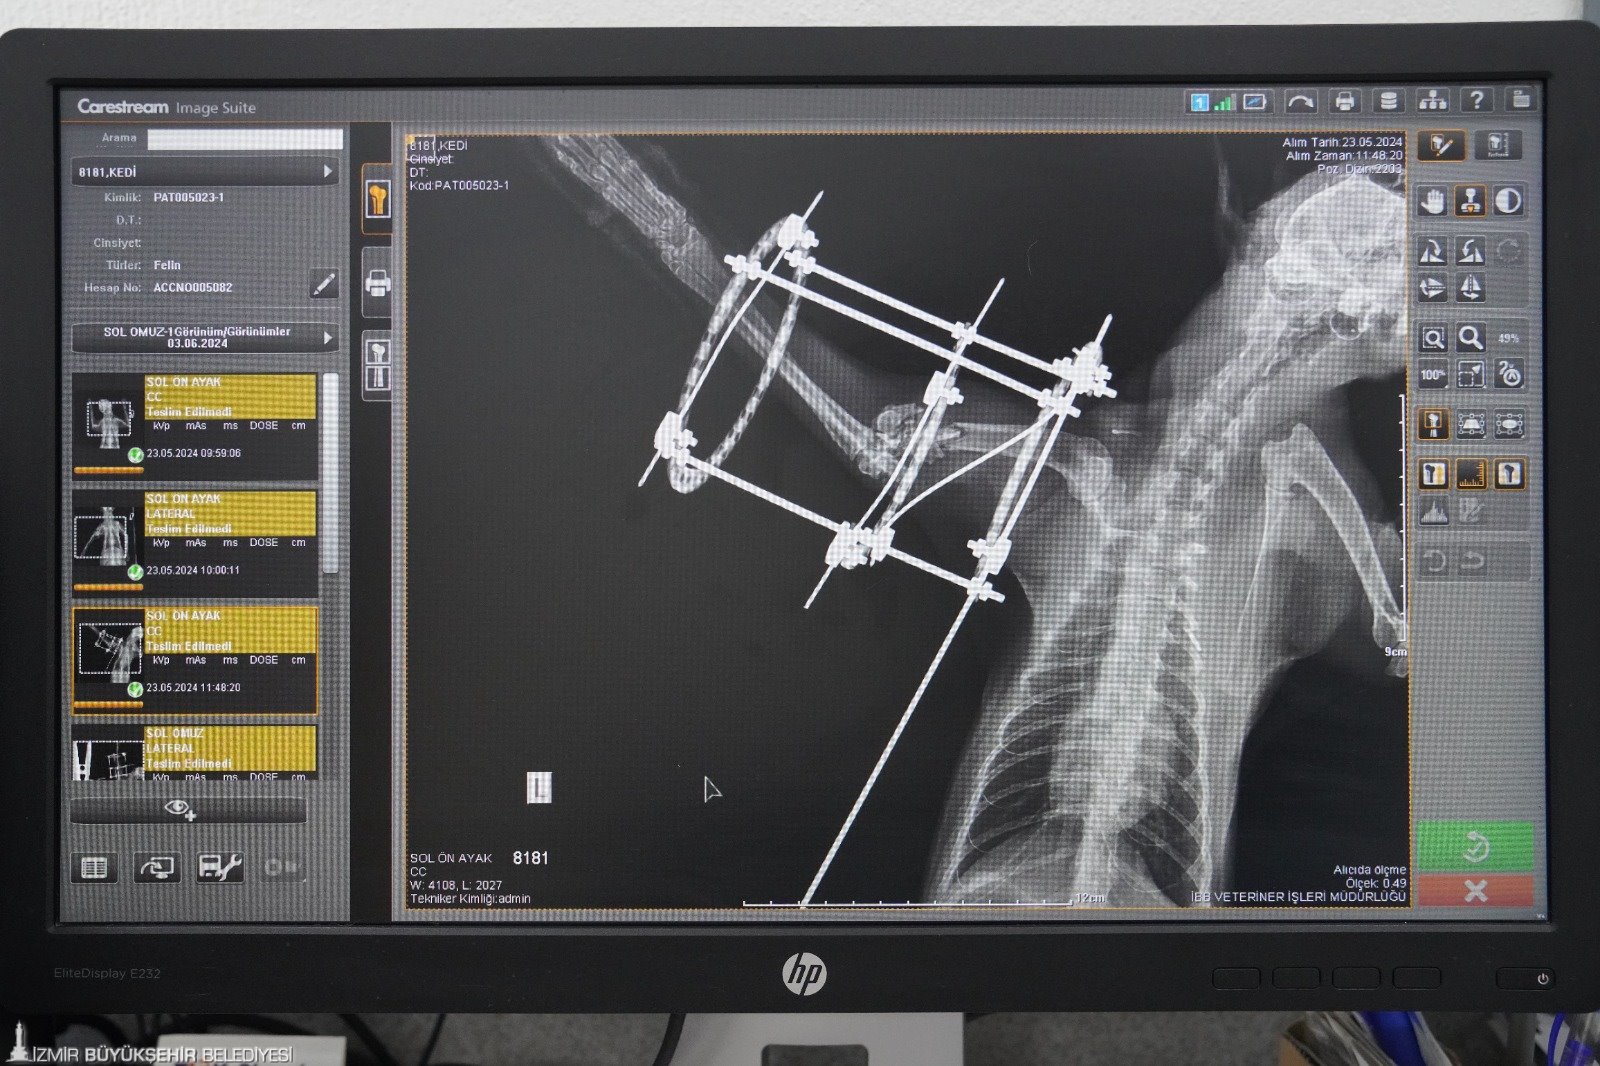

Özel aparatla sabitlendi

Ameliyat hakkında bilgi veren Veteriner Hekim Mehmet Uysal, ortopedi biriminde kedinin bacağının durumunu tespit ettiklerini belirterek, “Bacağının ciddi şekilde parçalandığını gördük. Burada sağlığına kavuşması için hemen gerekli cerrahi tedaviyi uyguladık. Bacağında parçalanan kemikleri özel bir aparatla sabitledik. Güvenli bir yöntem olduğu için bunu tercih ettik. Kedimiz 25 gündür bu şekilde tedavi altında. Bir süre sonra bu taktığımız aparatın kırıklar üzerindeki etkisine bakacağız. Bacak iyileşmiş olursa çıkaracağız. Şu anda sağlığı ile alakalı bir problemi yok. Keyfi yerinde. Bacağını nasıl kullanacağını öğreniyor diyebilirim” diye konuştu.

Şimdi sıra sıcak bir yuvada

Bu yöntemin zorlu ve maliyetli olduğunu da aktaran Uysal, “Biz böyle bir tedavi uygulamamış olsaydık kedinin bacağını ampute etmek zorunda kalacaktık. Çünkü iyileşme olasılığı çok düşük bir kırık. Biz bu şekilde şans vermek istedik. O da bizim tedavimize çok güzel bir şekilde cevap verdi. Muhtemelen de iyileşip buradan gidecek. En büyük temennimiz kendisine yuvasının kapısını açacak iyi yürekli bir aileyle birlikte buradan ayrılması” dedi.